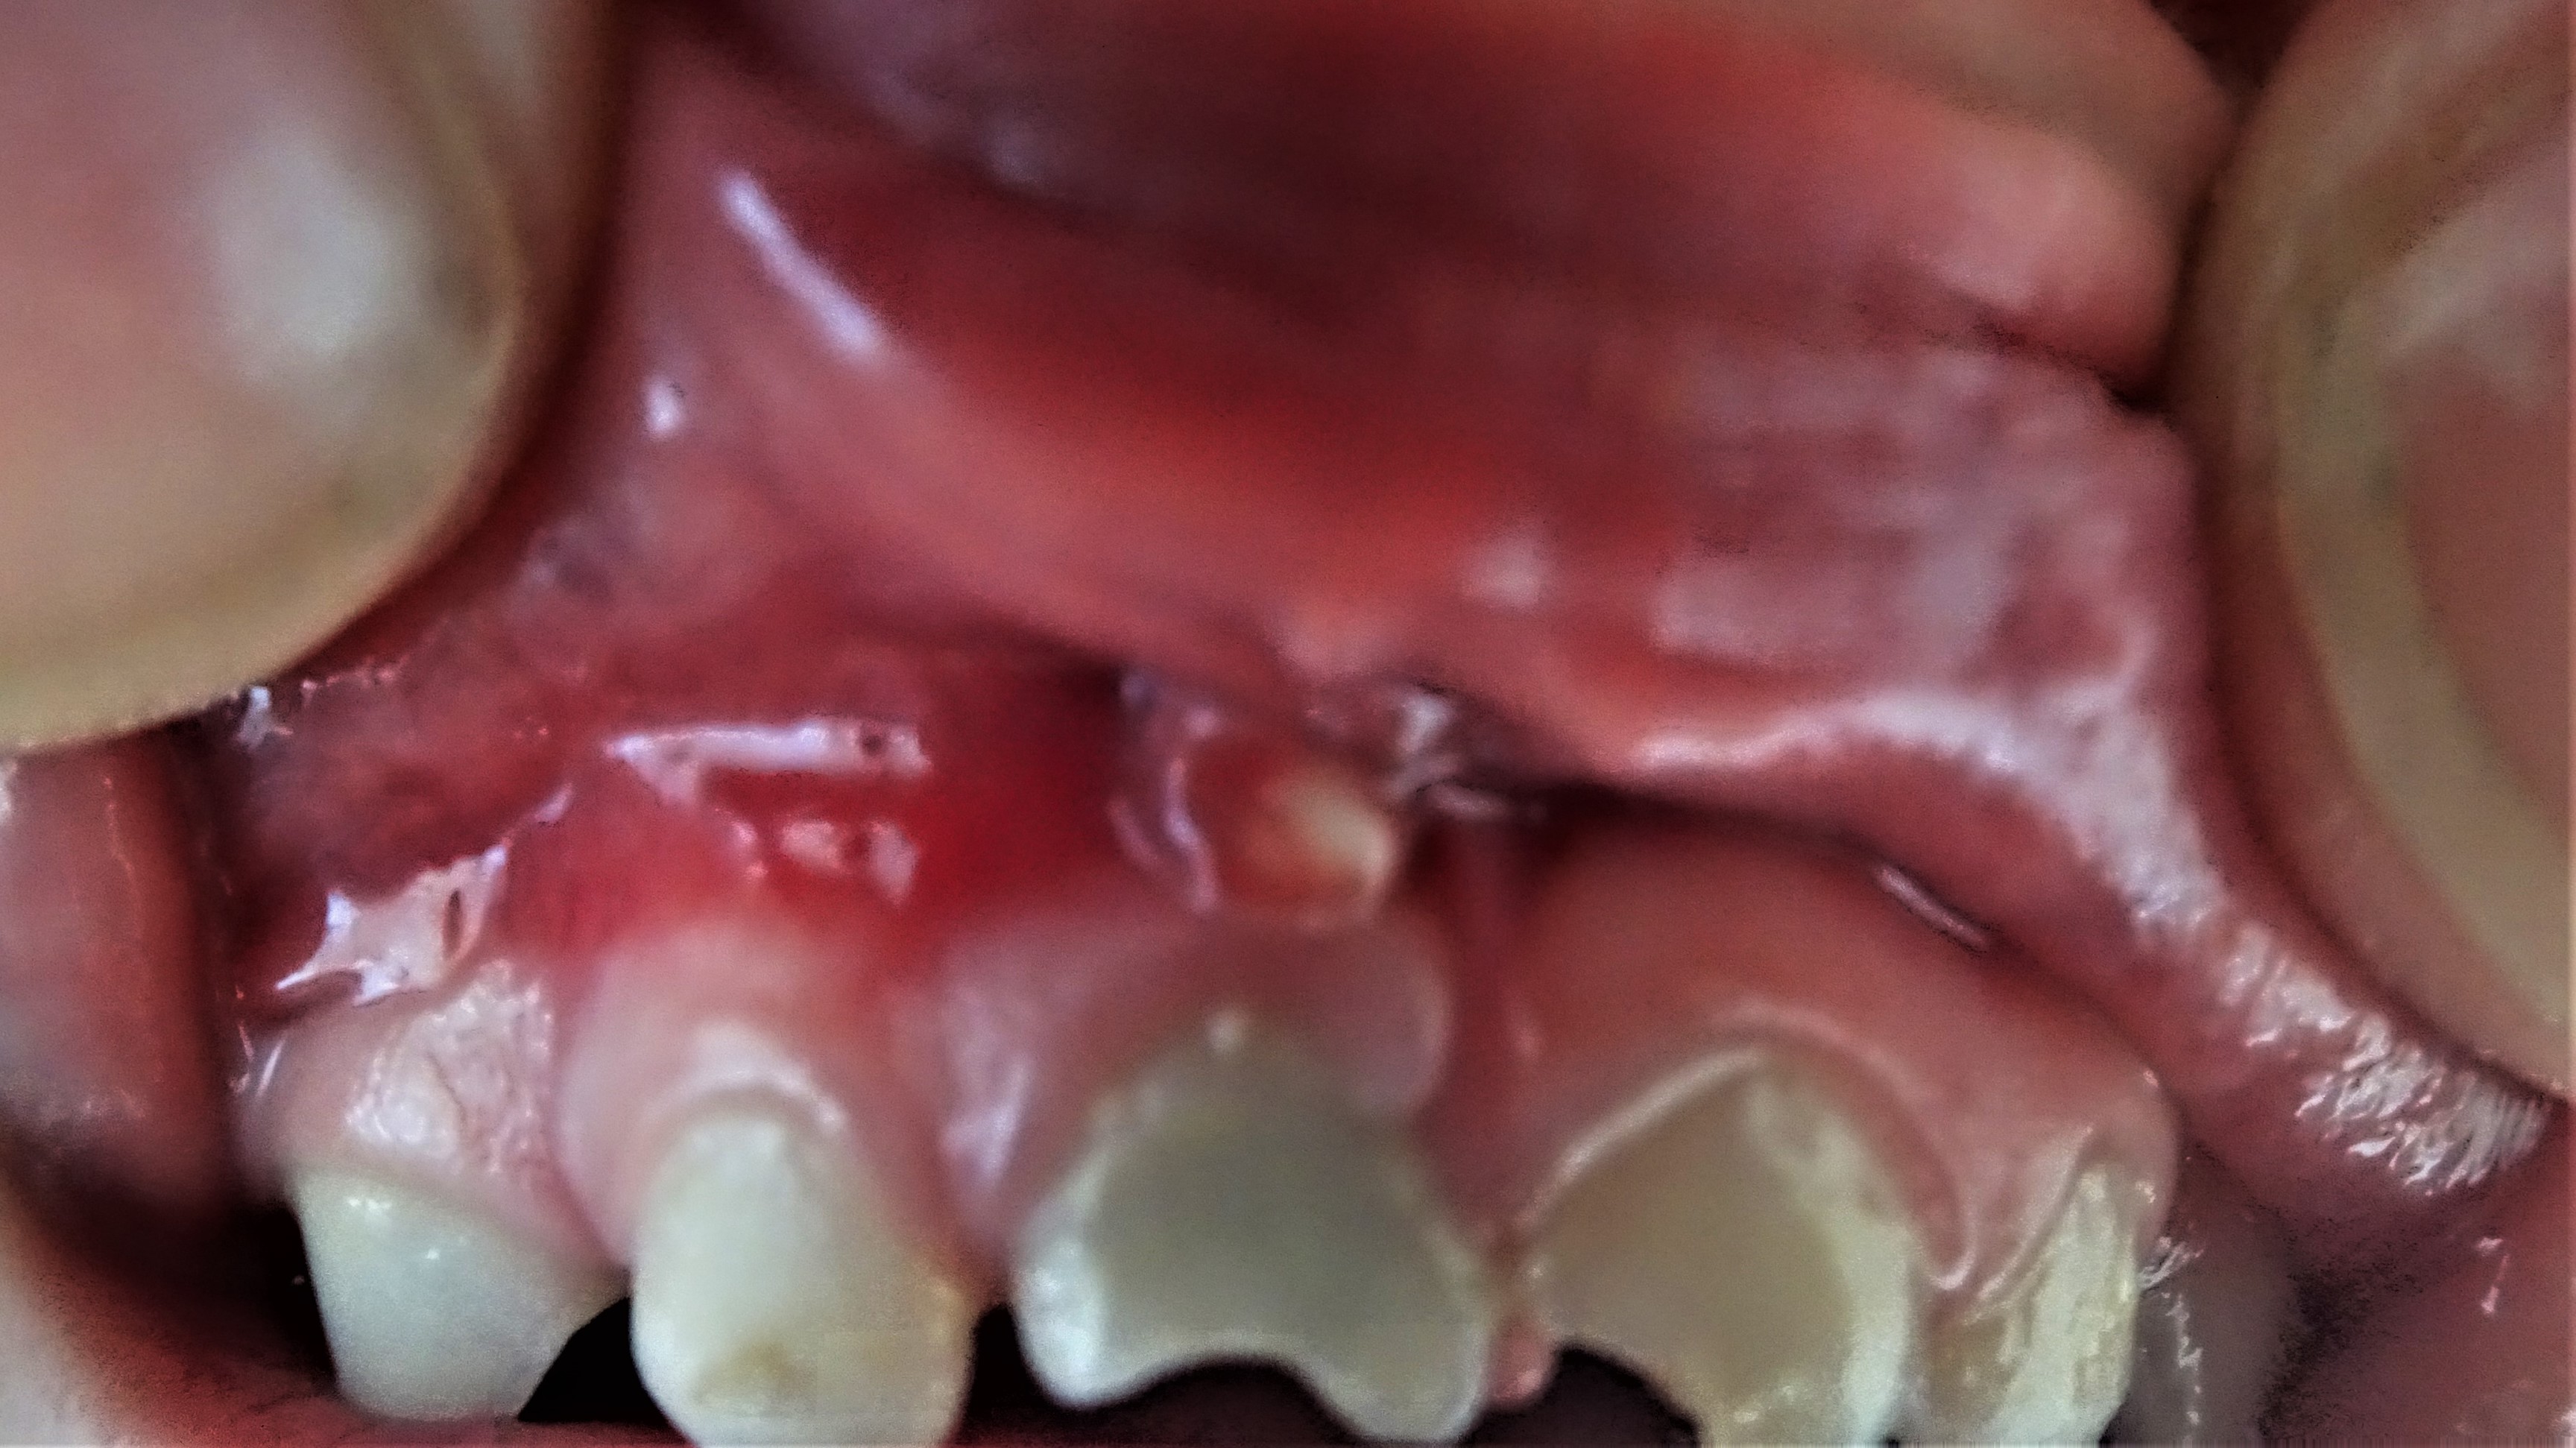

Mijn dochter van net 2 jaar oud, heeft 3 maanden geleden bij een val een stuk van haar voortandje afgebroken. We zijn de kindertandarts geweest en het leek er verder rustig uit te zien, geen last met eten en drinken. Het tandje is wel grijs geworden. Aan de achterkant, waar het breukvlak zit, is het heel donker. Ze heeft sindsdien regelmatig slechte adem. Afgelopen week mocht ik haar tandjes niet meer poetsen en zag ik dat het boven het tandje erg rood was en er een puskopje op het tandvlees zit.

Ik heb twee foto's toegevoegd.